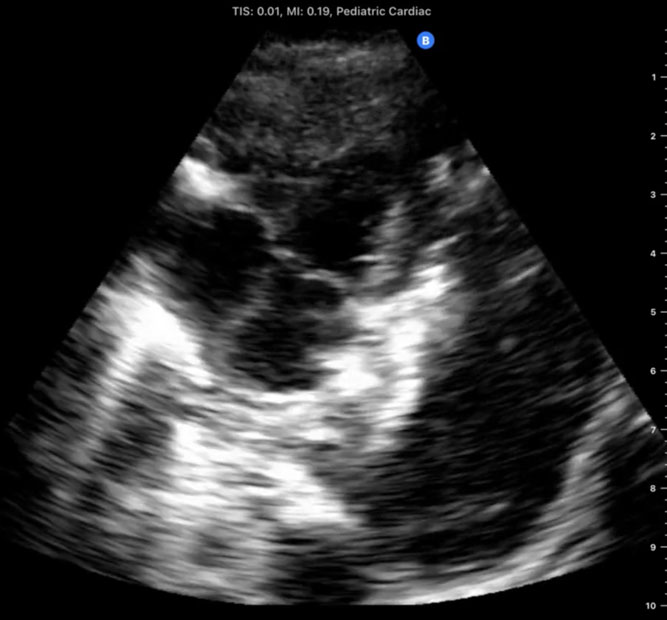

A 6-month-old infant is rushed through the emergency room directly into the Pediatric Intensive Care Unit (PICU) at the Mother and Child Hospital of N'djamena in Chad, Africa. His chest is barely rising with each rapid, shallow breath. A physical examination reveals diminished breath sounds on the left and an oxygen saturation of 80%. Despite being one of the largest hospitals in Chad, it has no portable X-ray machine available. One of our team members on this expedition to Chad brought a personal handheld ultrasound device (iQ, Butterfly Network, Inc, Guilford, CT, USA). Urgently, we performed a point-of-care-ultrasound (PoCUS) evaluation using a left midaxillary and subcostal views, which revealed a huge pleural effusion that was compressing the left lung. Pleurocentes is was guided by the handheld ultrasound, with an almost immediate resolution of the child's respiratory distress. An inspection of the thick fluid drained suggests that the likely cause was tuberculous pleural effusion (TPE).[1]

First-hand experience of recent expeditions to low-resource countries (eg, Chad and Sudan), as well as conflict zones such as the Ukrainian front lines following the Russian invasion on February 2022, reveals the substantial clinical utility that PoCUS may have, particularly when other imaging modalities are unavailable. During a recent expedition to Chad, a portable handheld ultrasound device directly assisted in making critical diagnoses and performing life-saving interventions in several men, women, and children. In total, 12 patients (mean age 14.9 years) were managed with the aid of PoCUS with the most common scenarios being trauma after motor vehicle accidents, respiratory failure, and obstetric complications. The most frequent study types performed were the Extended Focused Assessment with Sonography in Trauma (eFAST), cardiac, and lung studies. Within this group of patients, 2 died within this period (a 13-year-old girl with intra-abdominal perforation who traveled for 5 days to the hospital and a 12-year-old extremely malnourished girl who arrived in severe shock and required immediate CPR), and 2 remained with unknown outcomes but carried grave prognoses. PoCUS directed management in 75% of patients, including pulmonary edema in a laboring woman, an amoebic liver abscess diagnosis and ultrasound-guided drainage in a 3-year-old girl, a diagnosis of large pericardial effusion in a 10-month-old boy with Trisomy 21, and the diagnosis of intracranial hypertension using ocular ultrasound in an unconscious 13-year-old involved in a car accident as a pedestrian, suggesting intracranial bleeding.